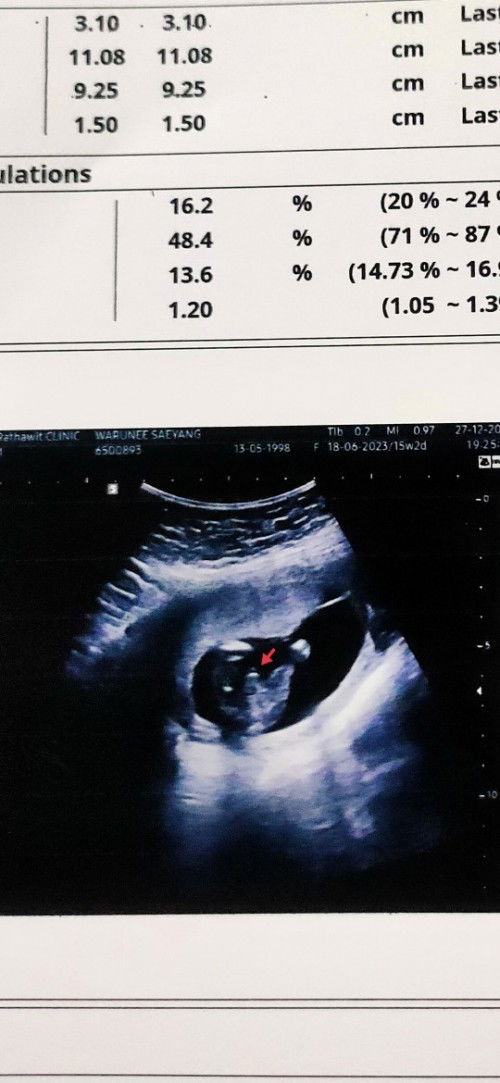

ซาวด์เพศลูก

#15w2d ไปซาวด์มาหมอบอกว่าผู้ชาย ผู้ชายชัวมั้ยคะ ลูกชายบ้านอื่นเห็นชัดแบบนี้มั้ยคะ